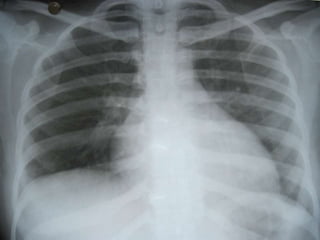

   Pt discharged

   Repeat chest X-Ray @ 2 weeks follow-up